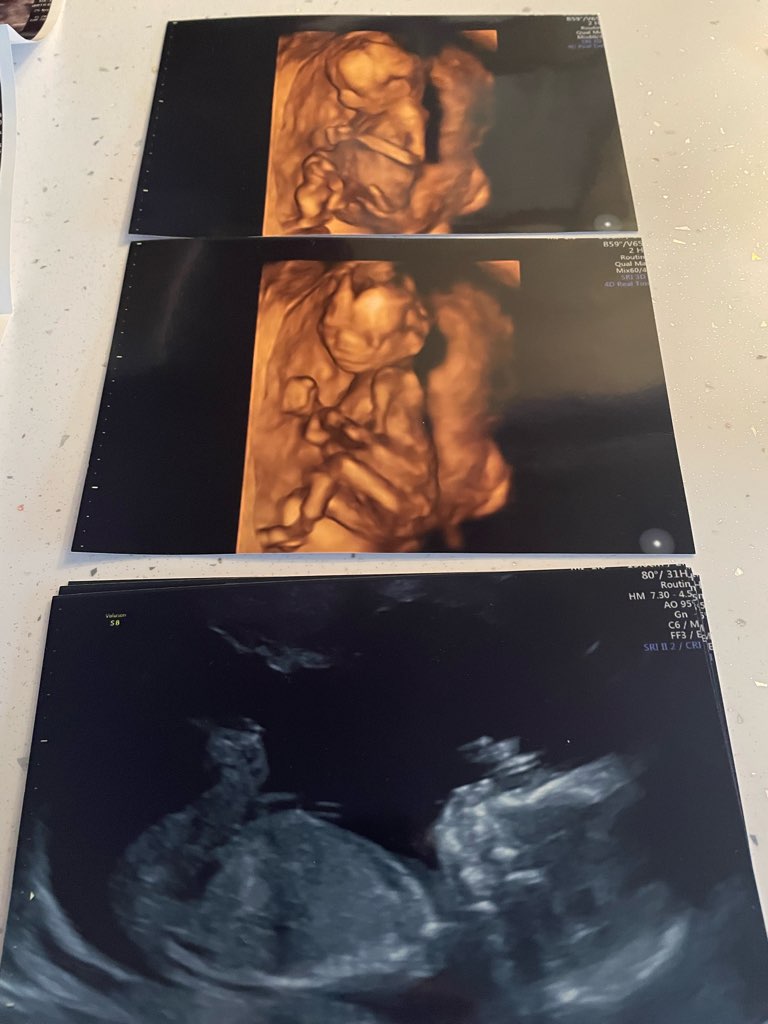

3 zdjęcie z 8+2 (21.5mm)

4 zdjęcie z 11+6 (genetyczne)

5 zdjęcie z 16+1 ( potwierdzenie płci )

6 zdjęcie z 19+3 (połówkowe )